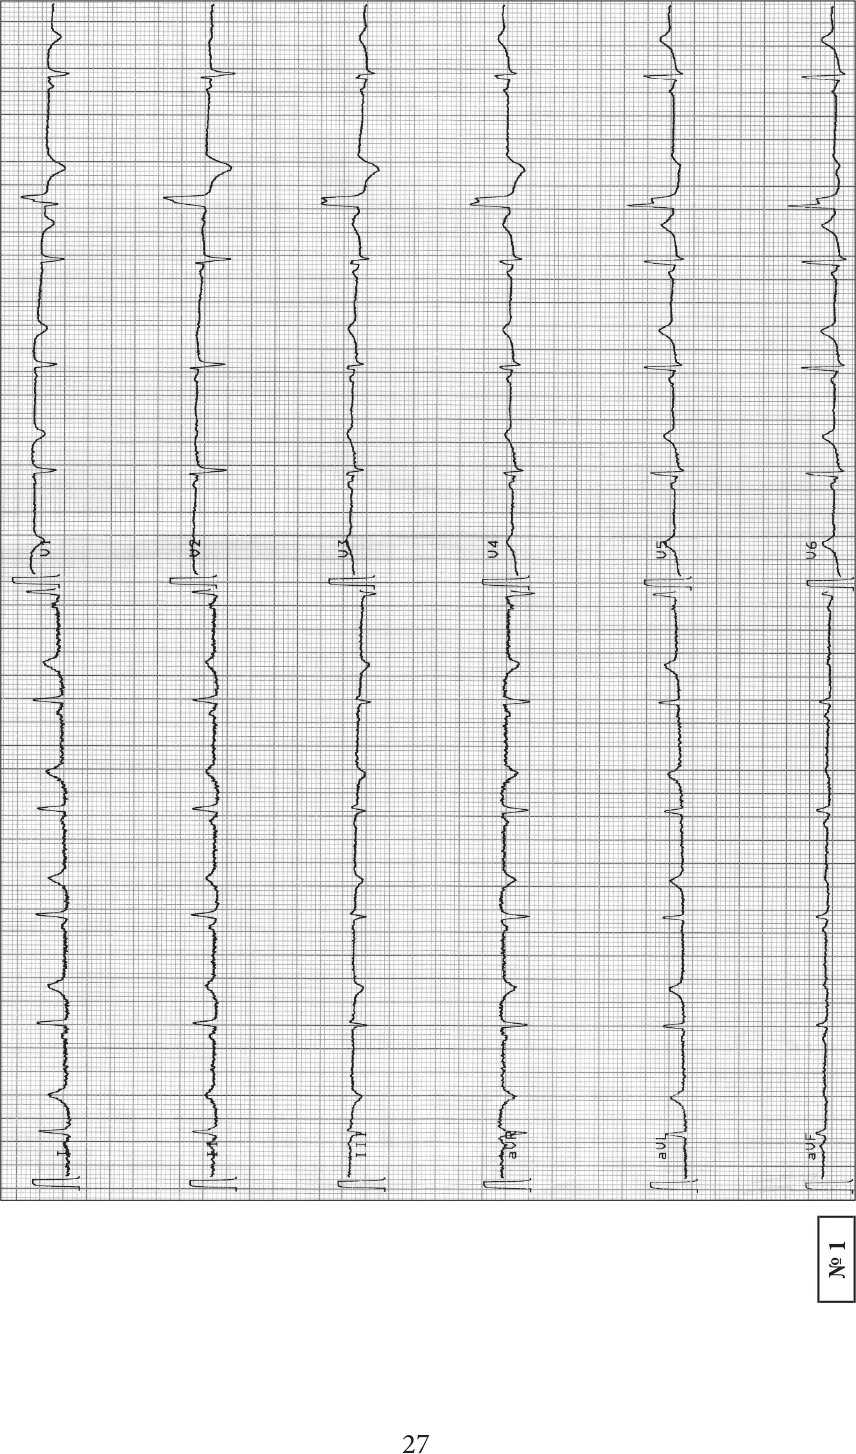

Издание содержит коллекцию из 300 часто встречаемых электрокардиограмм. Предназначено для практического закрепления теоретических знаний, полученных из учебников и учебных пособий по электрокардиографии, а также может с успехом использоваться в процессе о